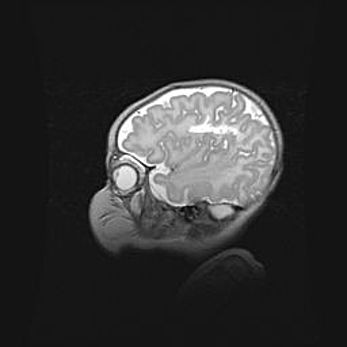

Наружная гидроцефалия с возможной атрофией височных областей.

Возраст: 28 дней

Вес: 3670 г

Пол: мужской

Окружность головы: 38 см

Срок гестации: 40 недель

Гидроцефалия головного мозга у новорожденных – это заболевание, которое характеризуется скоплением избыточного количества спинномозговой жидкости в желудочковой системе головного мозга в результате затруднения её перемещения от места выработки к месту поглощения в кровеносную систему или вследствие нарушения абсорбции. При открытой наружной форме гидроцефалии у новорожденных расширяются и переполняются субарахноидные пространства.

При нормотензивных  формах,  которые,  как  правило,  являются  следствием  перенесенных ишемических  повреждений  паренхимы  мозга,  возможно  сочетание микроцефалии  с нормотензивной гидроцефалией. В основе данных изменений лежит атрофия больших полушарий с преимущественной  локализацией  в  лобно-височных  областях.